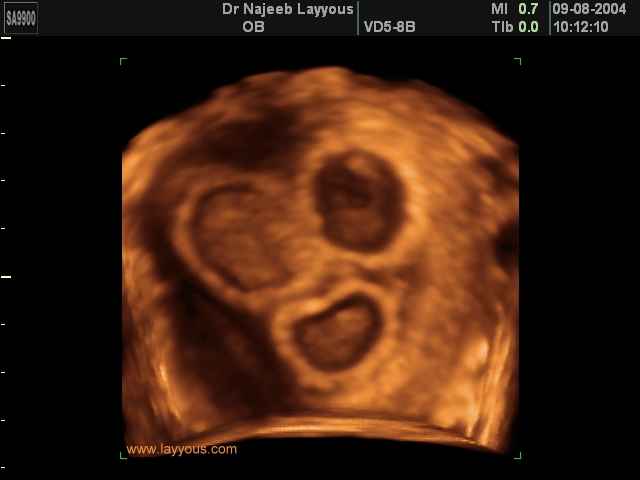

- صور لتوائم

صور لتوائم بجهاز الالتراساوند ثلاثي الأبعاد | الدكتور نجيب ليوس